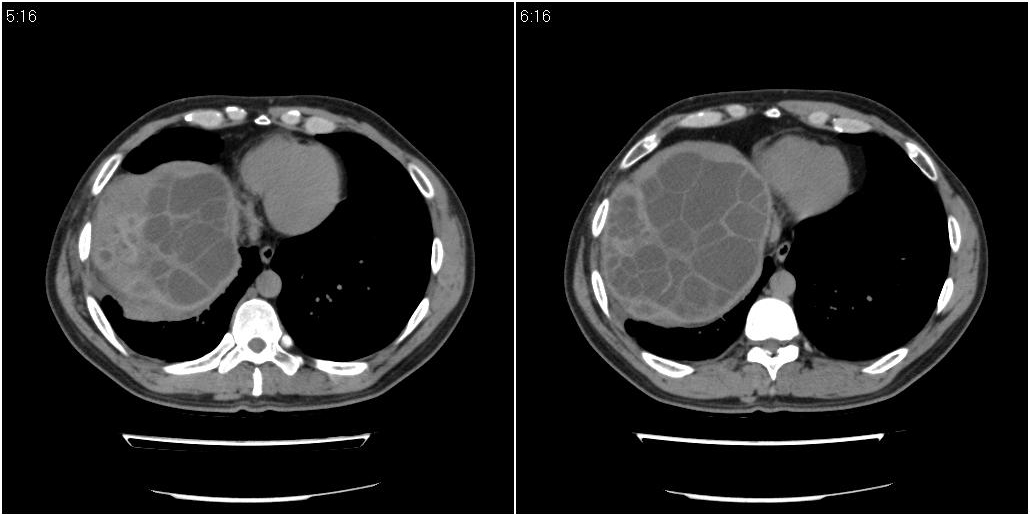

该患者70岁男性,手术后10年,现复查。2008年6月份本人曾经发过一极其类似的病例,只是部位略有差异。

肝脏多房性包虫囊肿

水上浮莲征,肝包虫囊肿。

肝脏及右侧胸腔包虫病。

浮莲征 肝包虫囊肿

大囊套小囊!肝脏多房性包虫囊肿